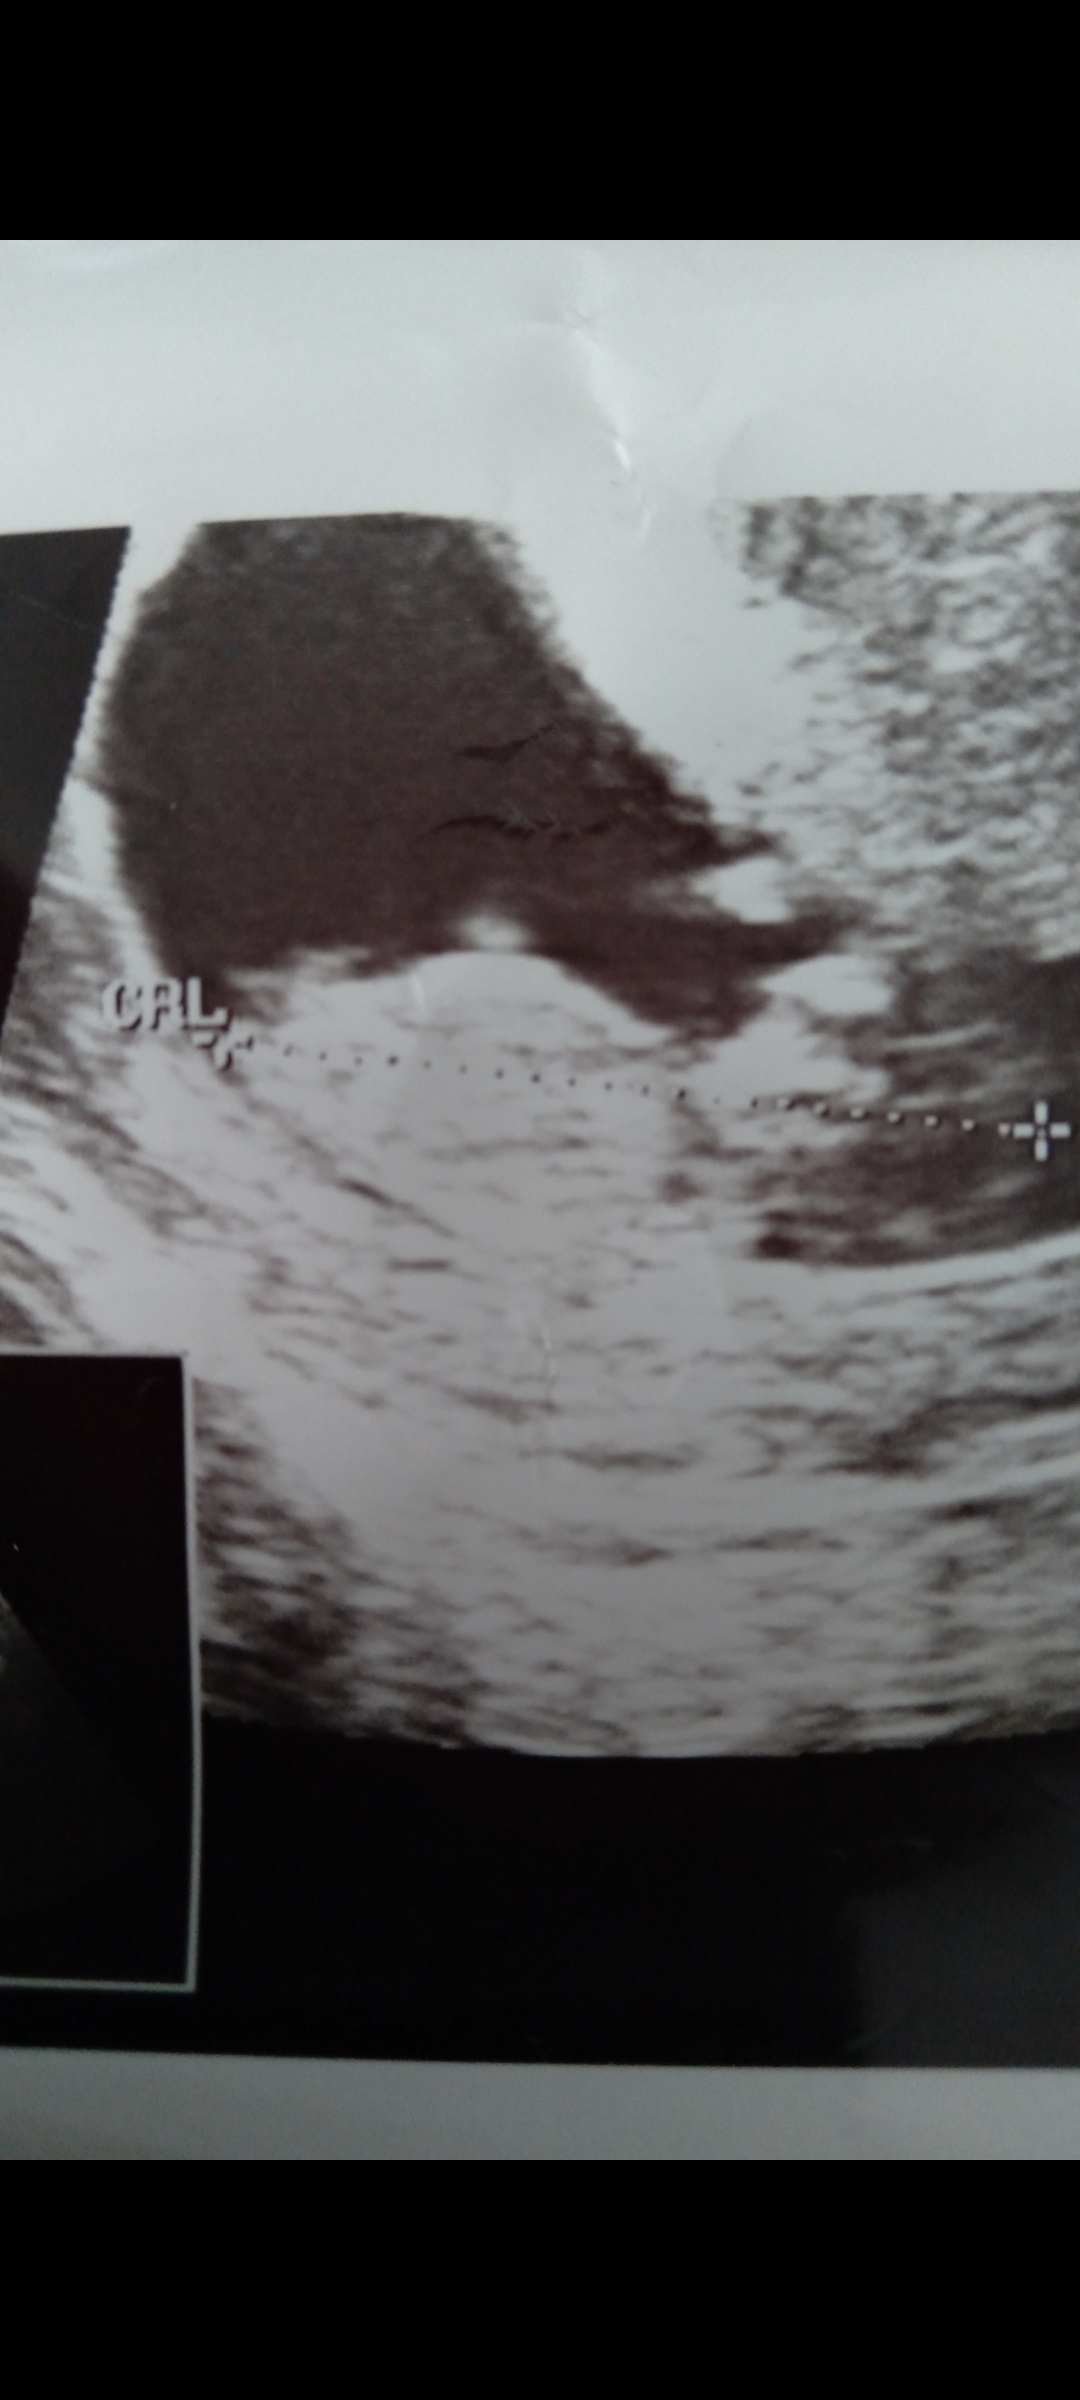

• Screenshot_20221119-153301_Gallery.jpg

Screenshot_20221119-153301_Gallery.jpg

884,9 KB · Görüntüleme: 147